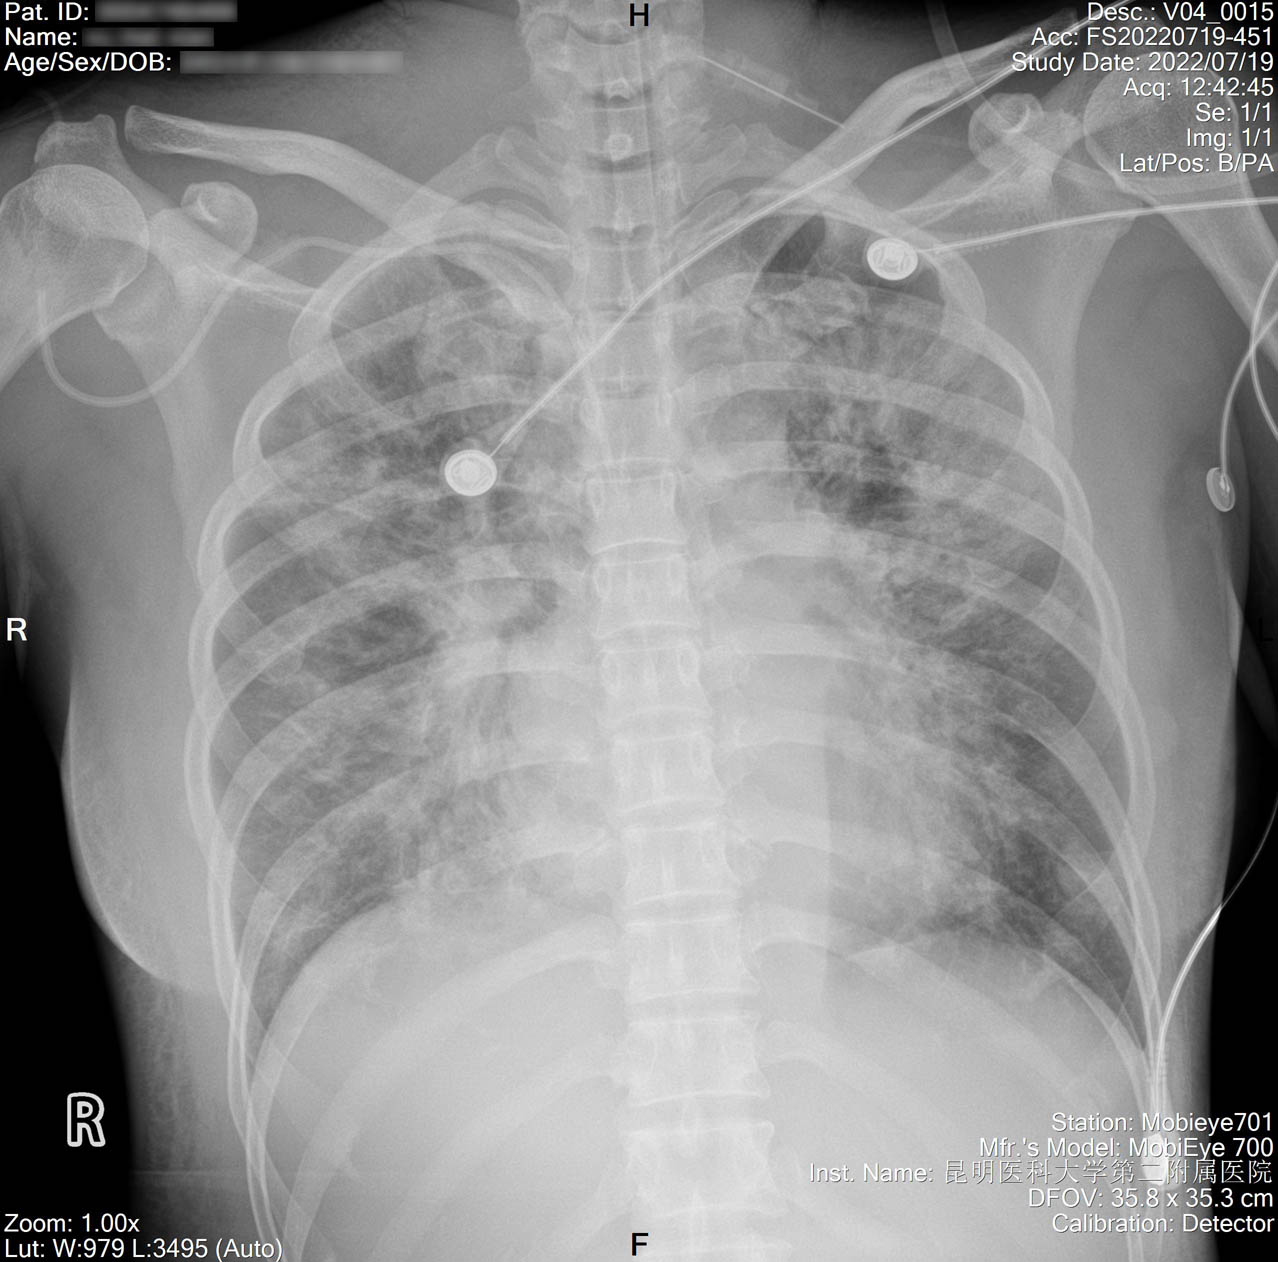

2022-07-16_胸片